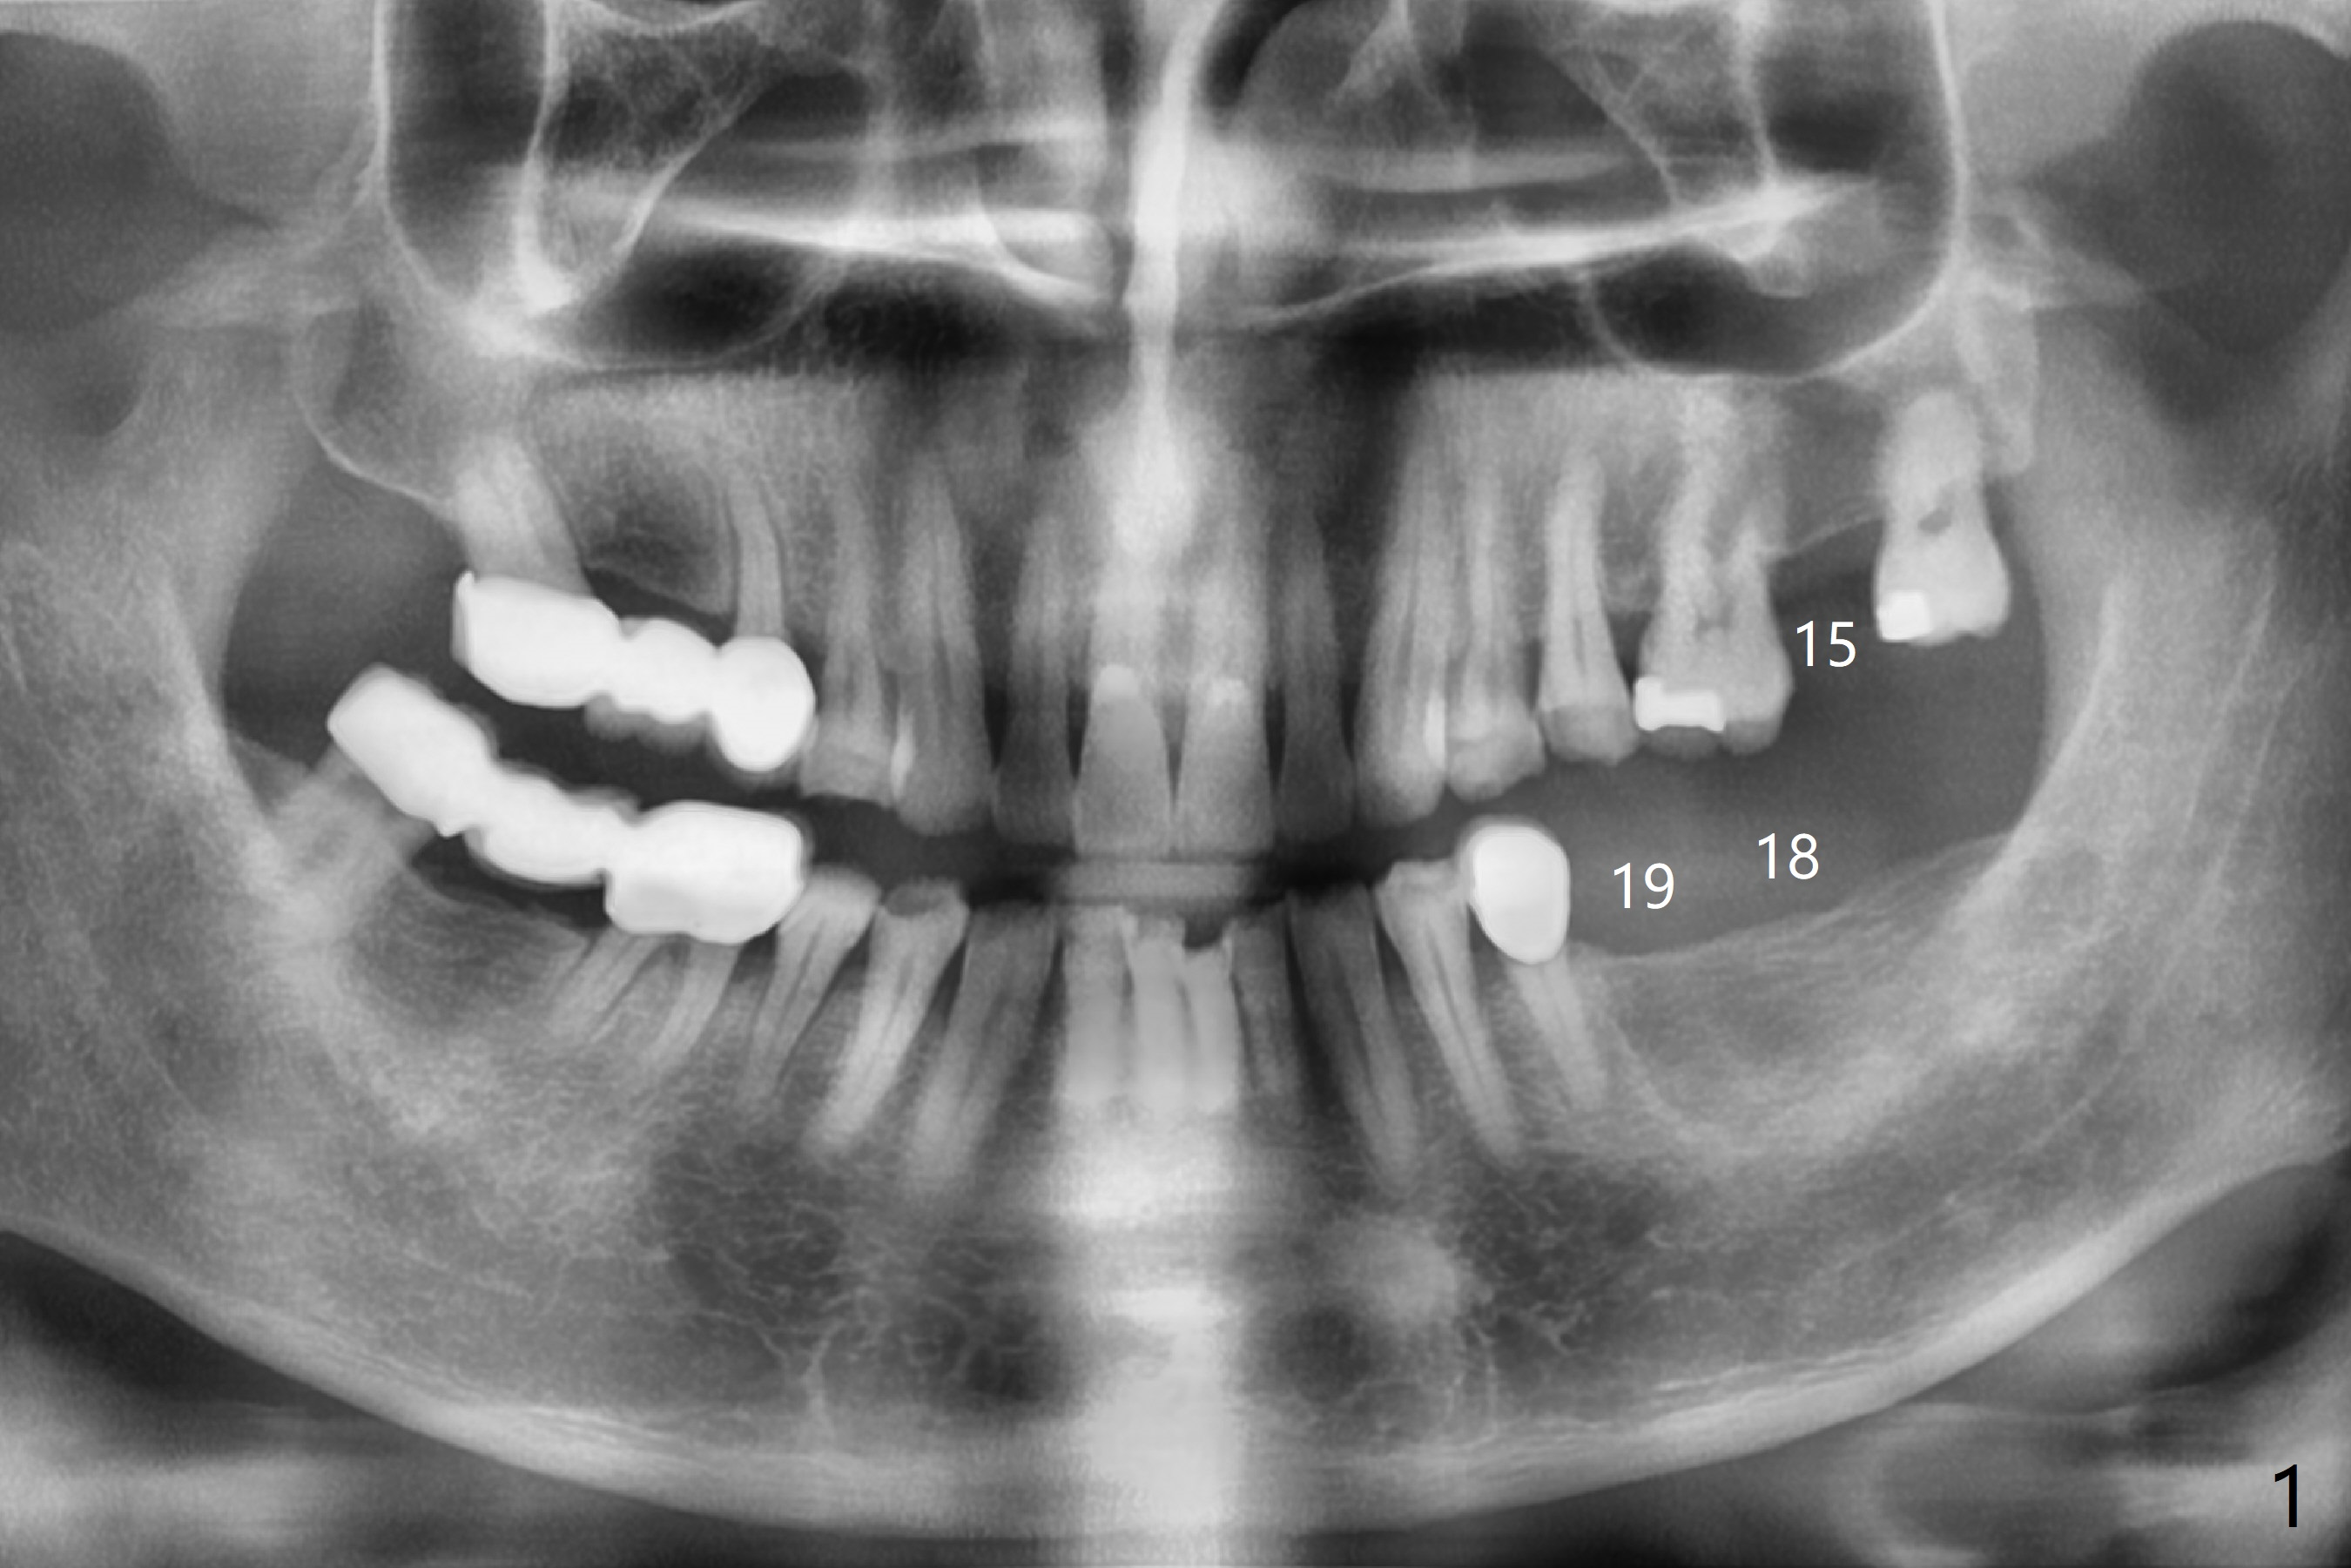

A 69-year-old man has 3 missing teeth: #15, 18 and 19 (Fig.1,2). He wants an implant at #19 first. A guide will be fabricated for #18 and 19 first. If he wants to have an implant at #18 later, the crown/abutment at #19 will be removed and an implant anchor will be used at #19 for #18 guided surgery. The upper model will remain or be resent to the guide lab for #15 guide if needed.